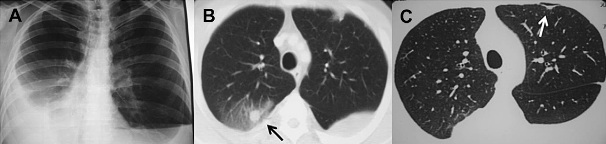

(圖:風(fēng)濕性關(guān)節(jié)炎肺部影像學(xué)異常1例)

2、肺炎和肺纖維化:少數(shù)風(fēng)濕性關(guān)節(jié)炎患者會(huì)出現(xiàn)發(fā)熱、咳嗽,病情進(jìn)展時(shí)可出現(xiàn)進(jìn)行性的呼吸困難,手指指端粗大,胸部X光片顯示:早期為肺門(mén)向雙側(cè)肺呈扇形網(wǎng)狀浸潤(rùn),后期為彌漫性、蜂窩狀陰影。肺纖維化男性較多見(jiàn),多在風(fēng)濕性關(guān)節(jié)炎發(fā)作后5~10年發(fā)病,也有先從肺部發(fā)病的。

3、肺風(fēng)濕結(jié)節(jié):風(fēng)濕性關(guān)節(jié)炎患者可在胸膜下,肺實(shí)質(zhì)內(nèi)多發(fā)性小結(jié)節(jié)陰影,也可單發(fā),前者可融合成塊狀,3~7毫米大小,后者為圓形,1~2厘米大小。肺中結(jié)節(jié)的出現(xiàn)、消失和空洞的愈合吸收與風(fēng)濕性關(guān)節(jié)炎活動(dòng)性和皮下結(jié)節(jié)的出現(xiàn)、消失基本同步。